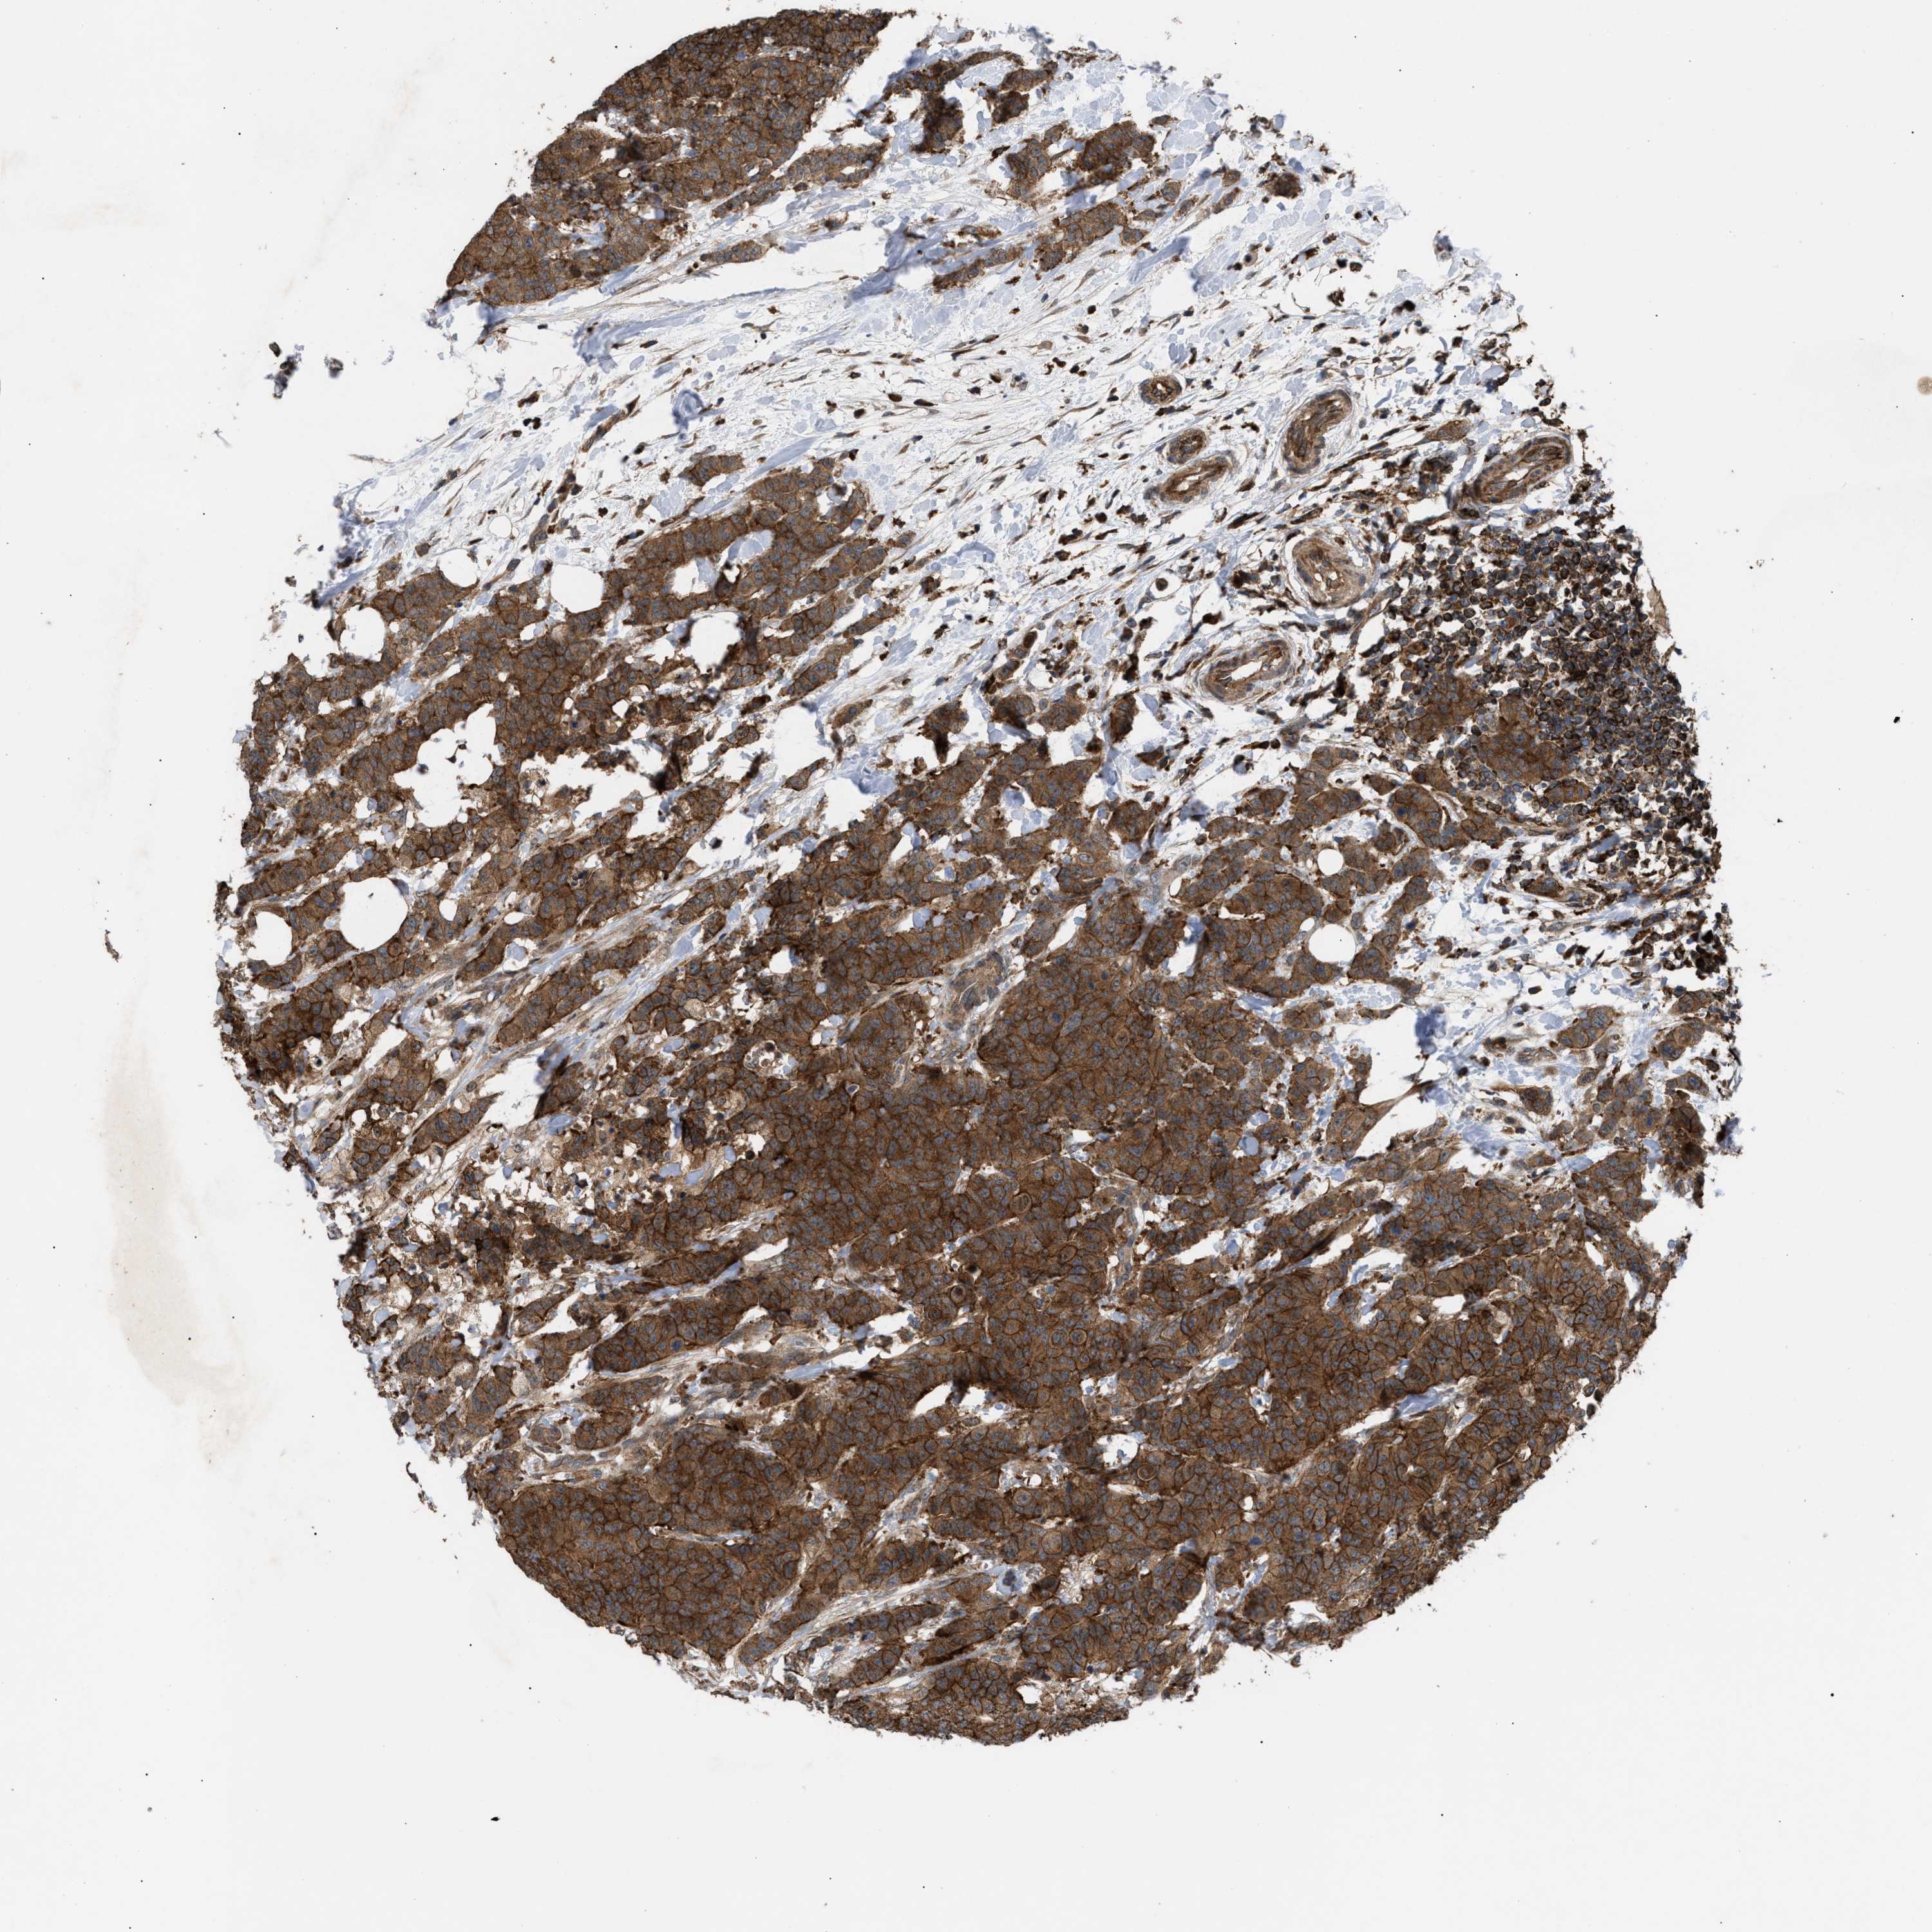

CANCER BREAST CANCER Show tissue menu

BRCA TCGA BRCA VALIDATION PROTEIN EXPRESSION